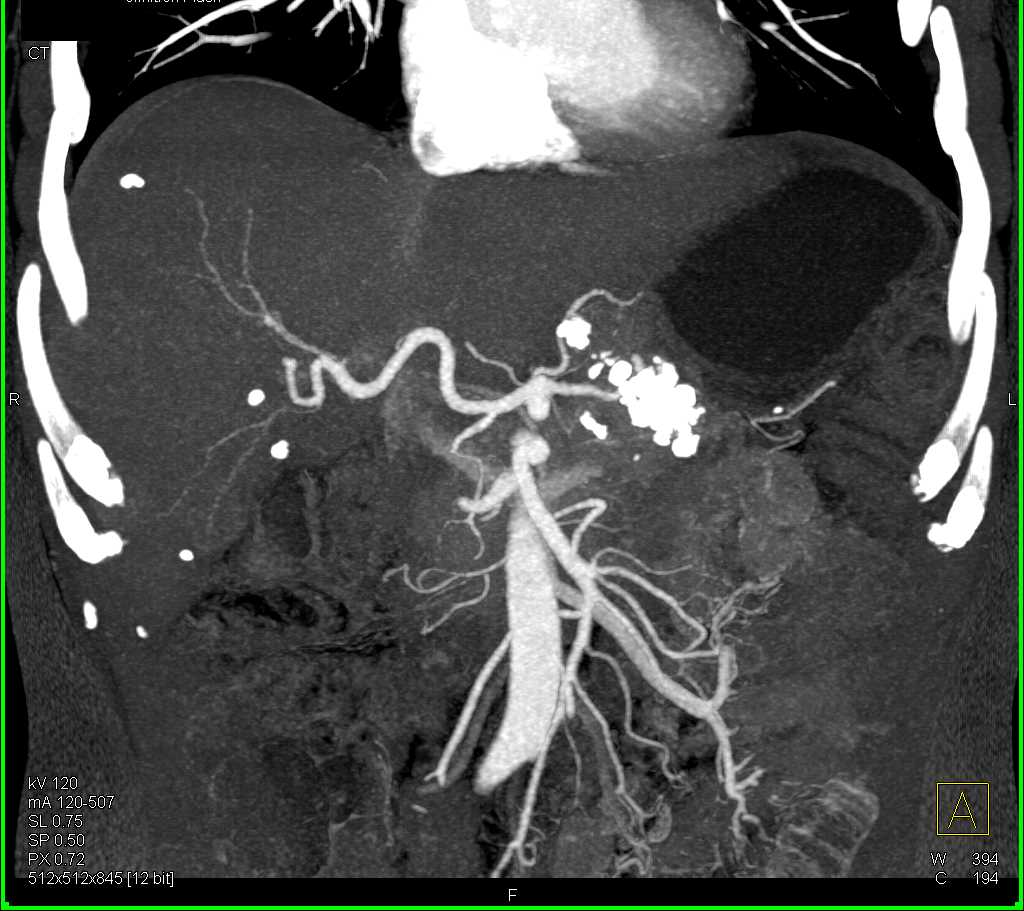

Neuroendocrine Tumor Pancreas